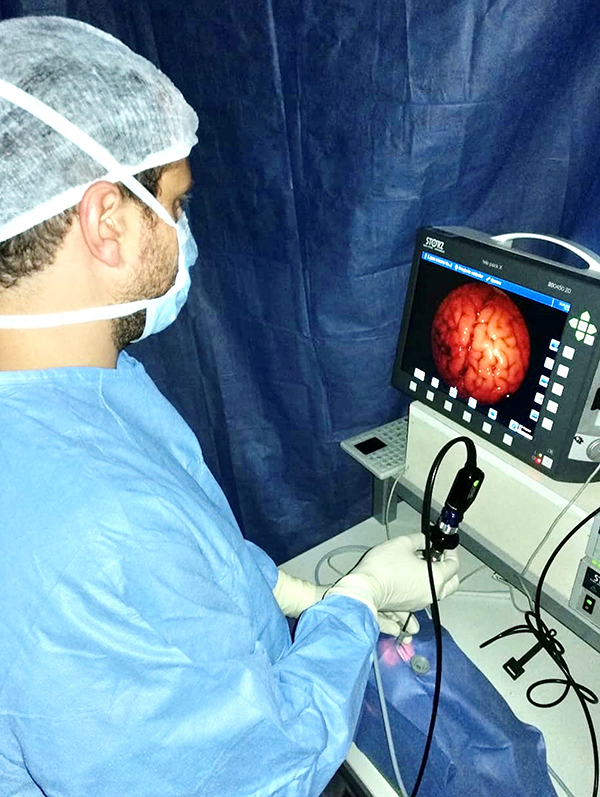

El modelo consiste en la utilización de un cerebro bovino (de preferencia utilizar la pieza completa) (fig. 1) y de pequeñas unidades de membrana amniótica, que se colocan envolviendo las tapas de botellas de plástico, para permitir la fenestración y dilatación de la misma (fig. 2 a-b). Éstas se disponen dentro de un recipiente esférico de poliestireno expandido (fig. 3 a-b), el cual se fenestra en la parte superior para permitir el ingreso del endoscopio. Para poder utilizar el monopolar debe colocarse dentro del recipiente el terminal del cable, que proviene de la consola, directamente en contacto con el tejido cerebral (fig. 4). Finalmente cerramos la esfera de poliestireno expandido y la llenamos por completo con solución fisiológica o agua corriente (fig. 5).

Para realizar la unidades de membrana amniótica utilizamos tapas de plástico color negro las cuales tapizamos del lado cóncavo con un fragmento de membrana amniótica de 5x5 cm. Para mantener la tensión utilizamos una banda elástica (fig. 2 b). Debemos rellenar la cavidad que quedó entre la tapa y la membrana amniótica con agua o solución fisiológica para lograr el medio acuoso que se encontrará una vez fenestrada la membrana y que simula el piso del III ventrículo (fig. 6). Para concluir colocamos la esfera sobre otro recipiente que sirve como base de sustentación y en la parte superior, donde teníamos las dos fenestras, colocamos dos trocares para el ingreso del endoscopio (no son requisito absoluto). Se utilizan dos entradas para duplicar el número de ejercicios (fig. 7). Este modelo innovador permite la biopsia y coagulación de tejidos (fig. 8) y la dilatación de membranas simulando un ejercicio de tercer ventriculostomía endoscópica.

Figura 6: Imagen del estudiante entrenando con el modelo de simulación en uno de nuestros cursos.